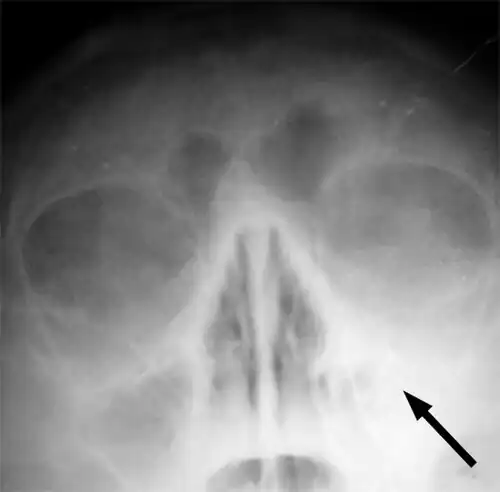

X-ray of left-sided maxillary sinusitis marked by an arrow. There is a lack of air transparency, indicating fluid in contrast to the other side.